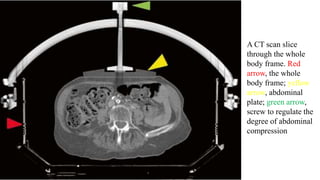

A CT scan slice

through the whole

body frame. Red

arrow, the whole

body frame; yellow

arrow, abdominal

plate; green arrow,

screw to regulate the

degree of abdominal

compression

A CT scanslice through the whole body frame. Red arrow, the whole body frame; yellow arrow, abdominal plate; green arrow, screw to regulate the degree of abdominal compression